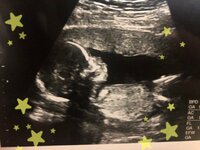

『ビッグダディ』として知られる林下清志氏の四女・都美さんが14、15日に自身のアメブロを更新。帝王切開レポートとして1月24日に誕生した第1子男児の出産時のエピソードを振り返った。

都美さんはこの日、帝王切開になった理由について妊娠8か月目に入った頃に医師から「赤ちゃんおっきいです」と言われたことだったと説明。「さほど気にすることではないと言われたので、そこまで気にせず過ごしてました」と明かすも、「赤ちゃんあんまり下に下がってこないね。それにおっきいからこのままだと帝王切開になるかな」と言われたそう。